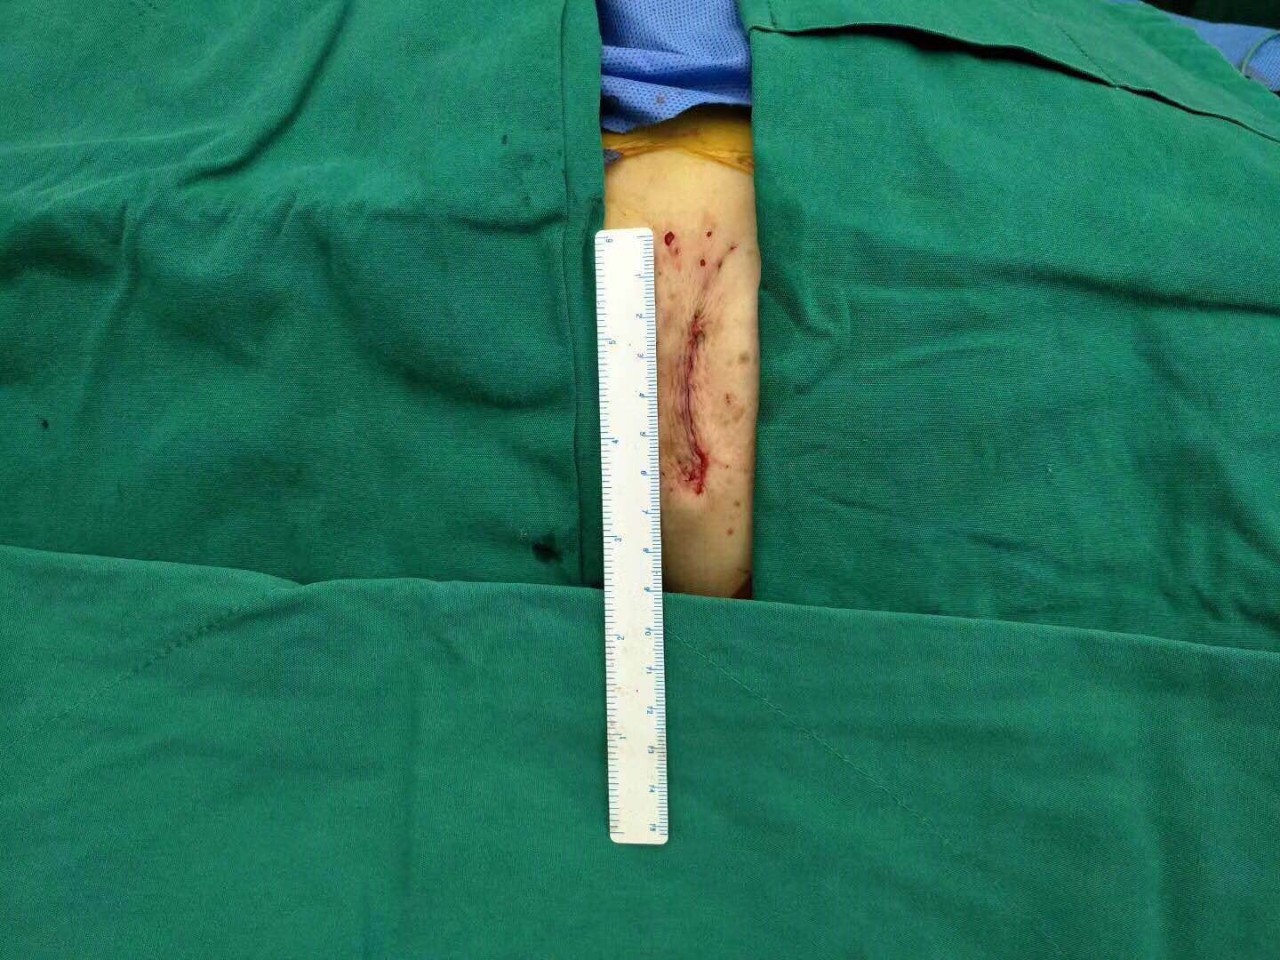

患者胸前伤口仅4厘米

整个手术过程非常顺利,仅耗1个半小时,胸骨肋骨无任何破坏,也无需体外循环,出血量未超过100ml。术后2小时老太太完全清醒过来并拔除气管插管,还能与医务人员轻松交谈。